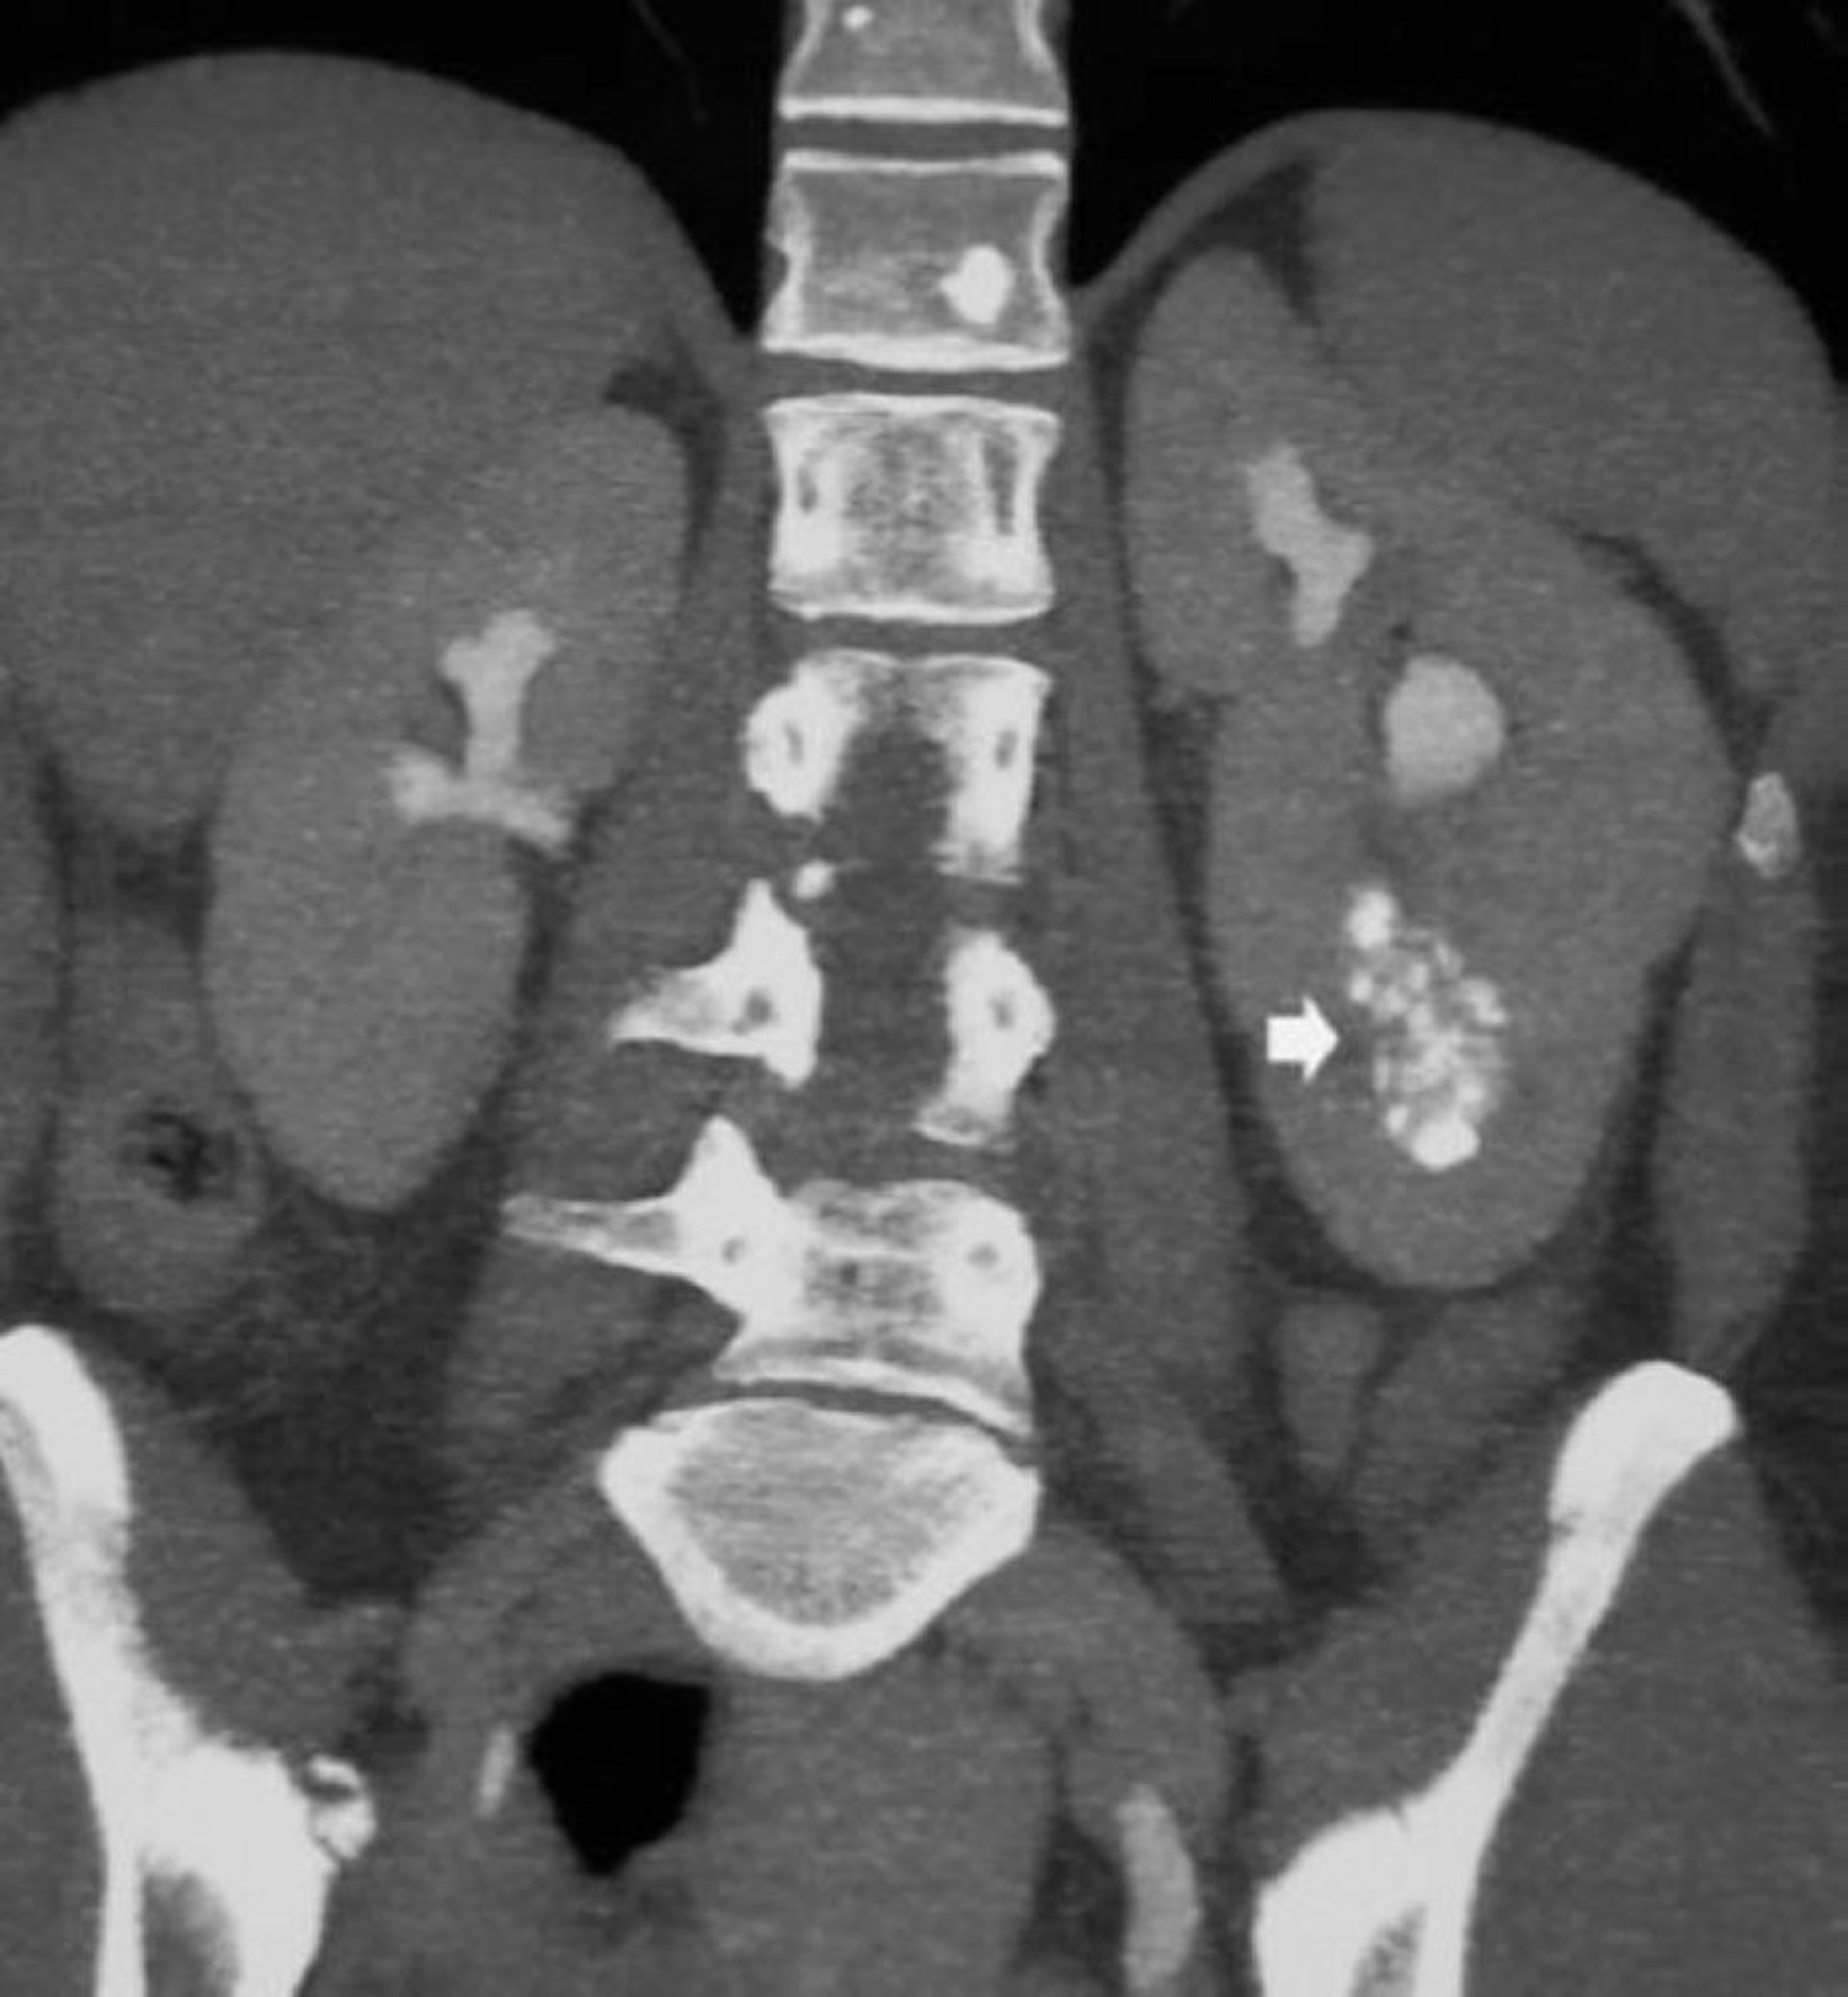

Diese Abbildung zeigt eine medulläre Nephrokalzinose und erweiterte kontrastmittelgefüllte Sammelkanäle bei einem Patienten mit einer Nierenschwammniere (Pfeil).

© Springer Science+Business Media

Die Diagnose wird üblicherweise durch CT bestätigt, aber Ausscheidungsurografie kann ebenfalls verwendet werden. Eine Ultraschalluntersuchung ist nicht hilfreich, weil die Zysten klein sind und tief im Nierenmark liegen.